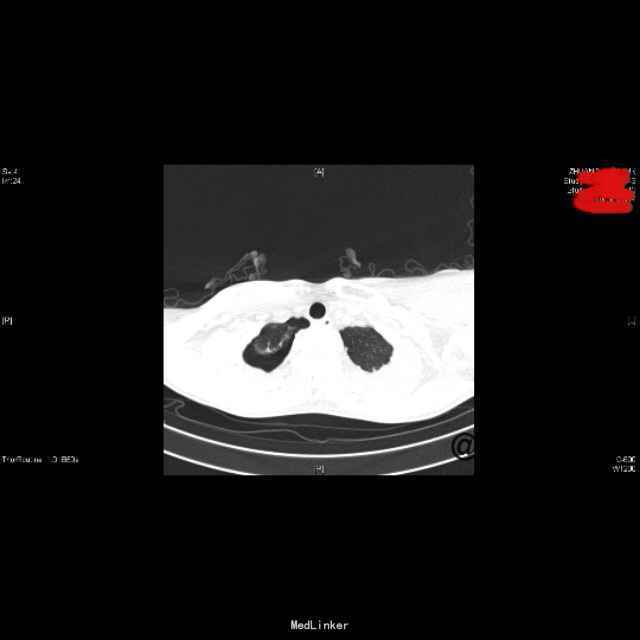

查体:右上肺呼吸音低,余无特殊;心脏、腹部查体未见异常。 辅查: (2015-10-27)行X平片(胸部)检查提示:右侧胸腔引流管置入后改变。 (2015-10-29)胸片:右侧气胸(肺组织压缩约10%),并右侧胸腔引流管置入后改变。 (2015-11-03)行CT(颈胸部CT)检查提示:1、右侧气胸,右侧胸腔积液,右侧胸膜增厚;2、右肺下叶良性硬化性小结节。 (2015-11-09)胸片胸部未见明显异常X线征象。 (2015-10-27)血生化:白介素-69.12ng/L、余无明显异常。 传染病四项、结核感染T细胞检测、大便、小便常规、血常规未见明显异常。 (2015-11-09)复查血常规:嗜酸性粒细胞百分数8.30%、余无明显异常。复查生化:未见明显异常。